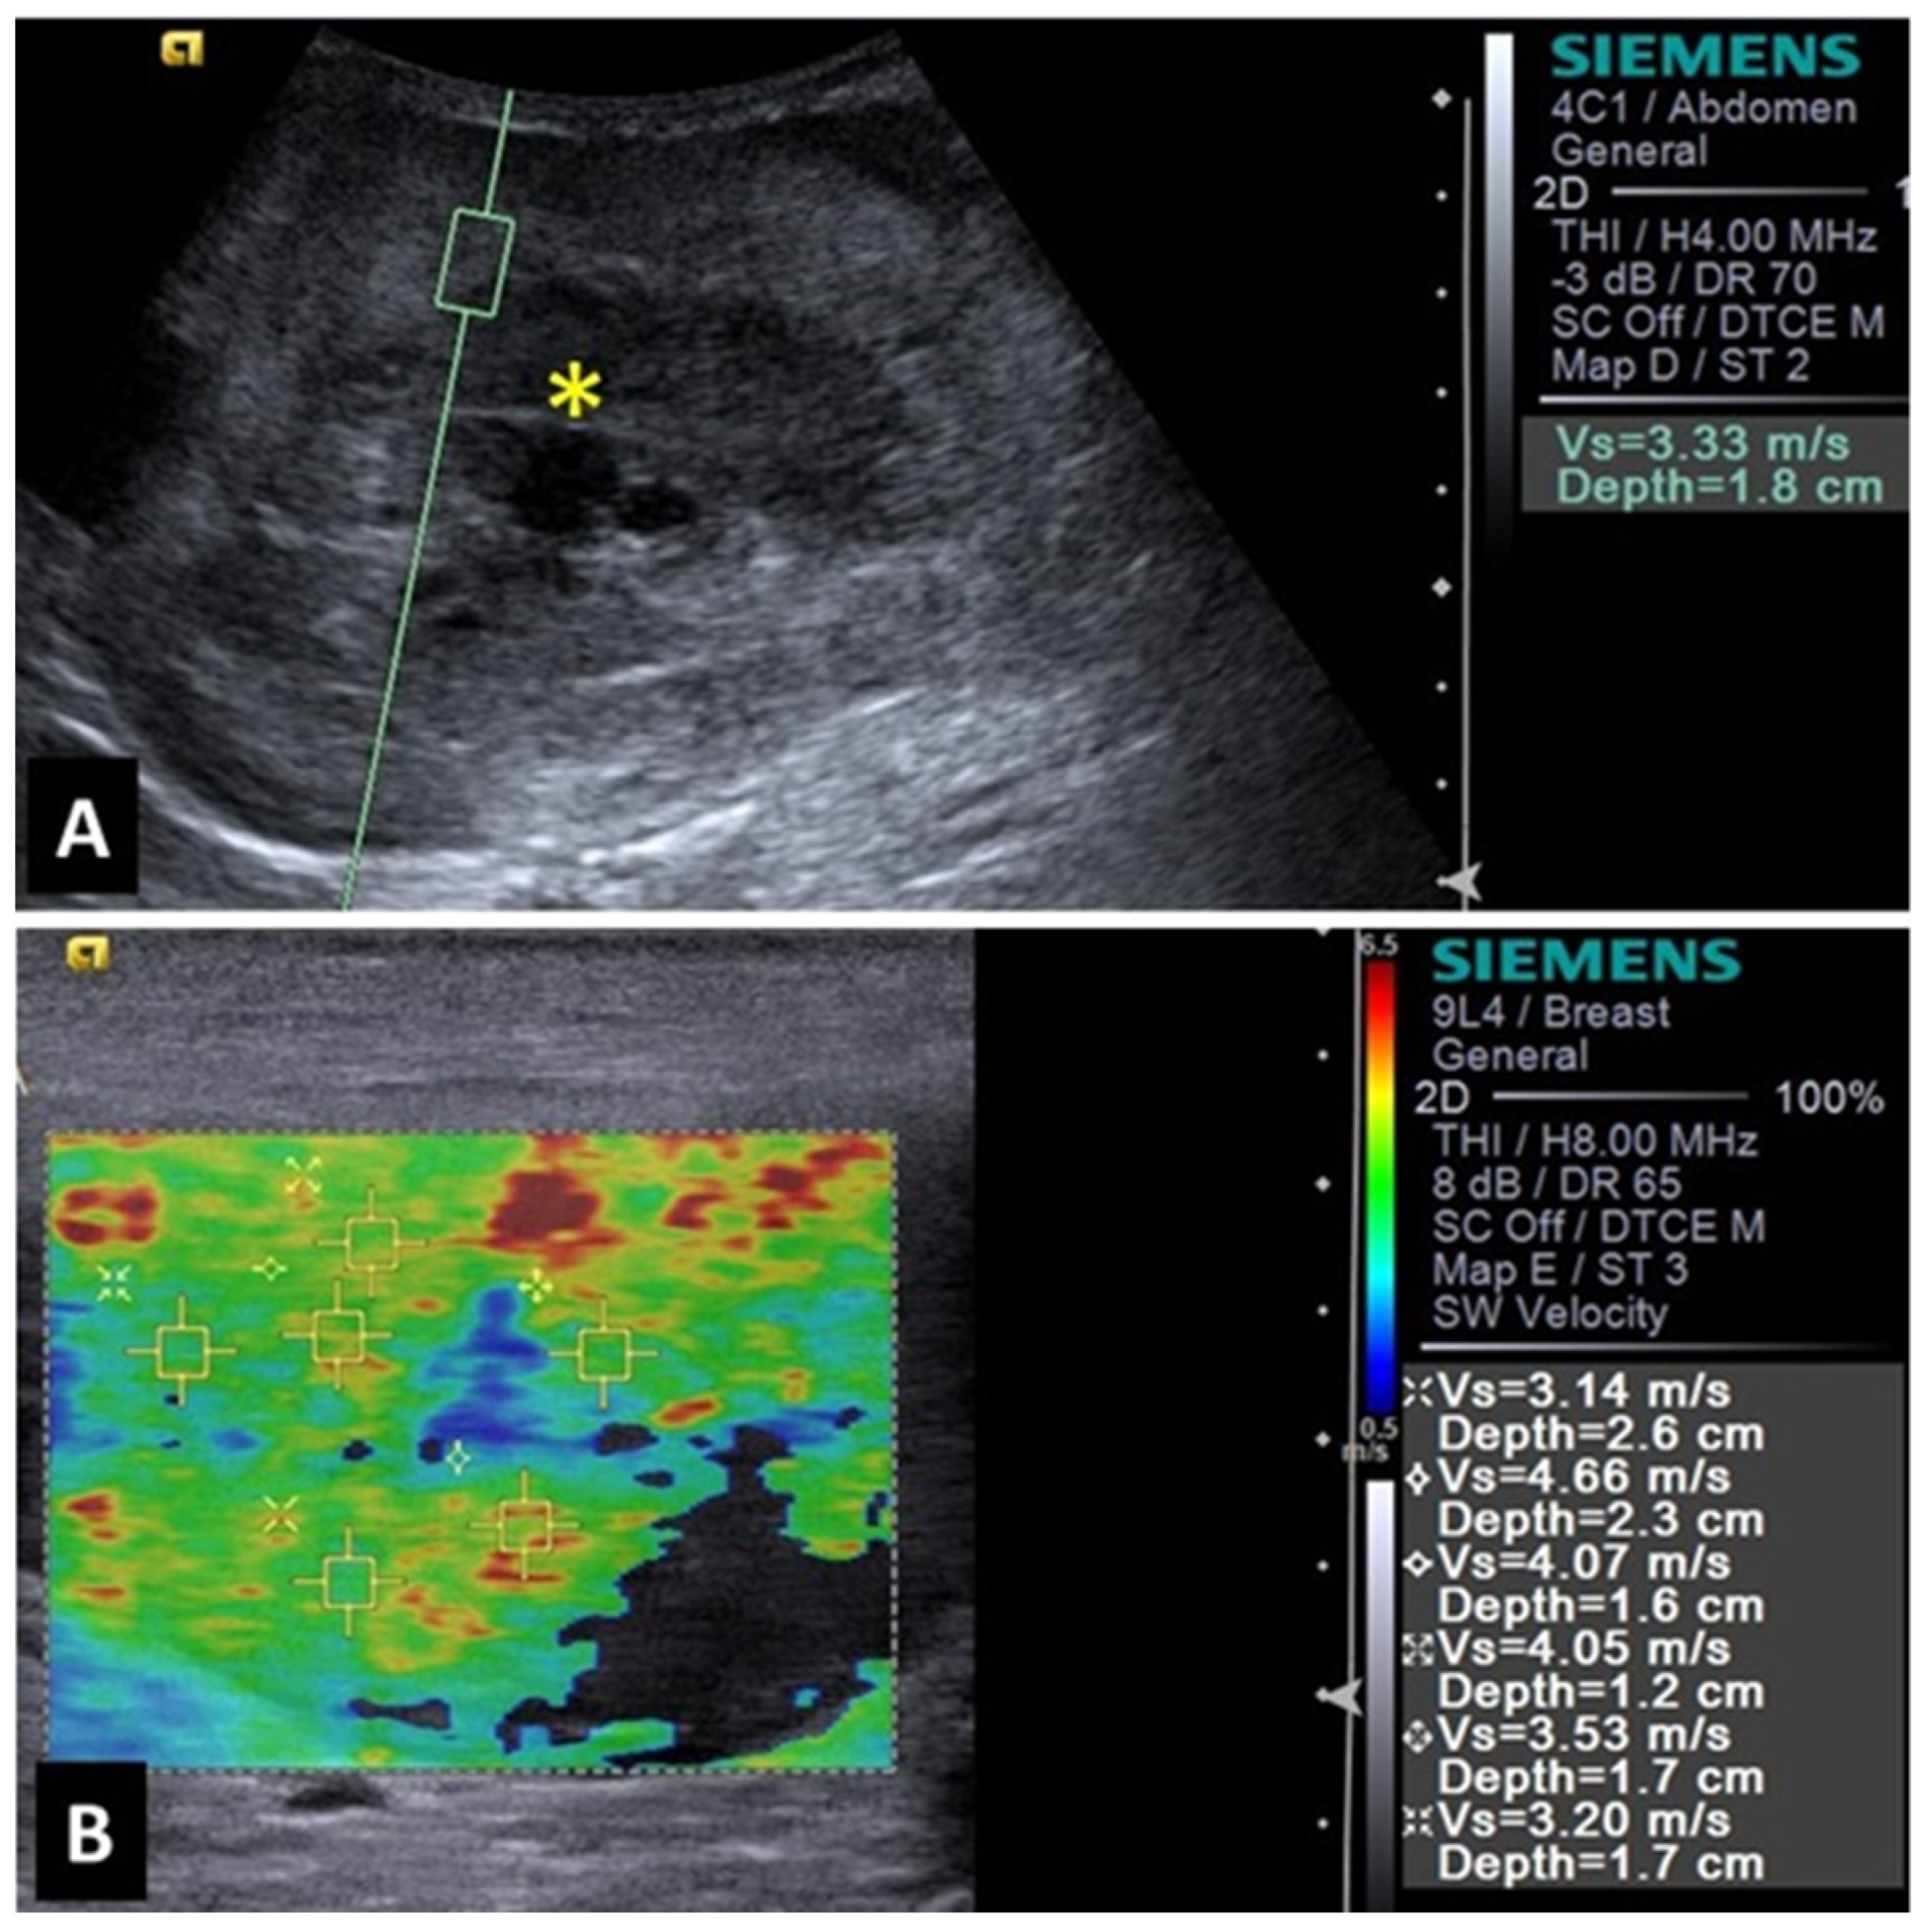

2.3. Spleen